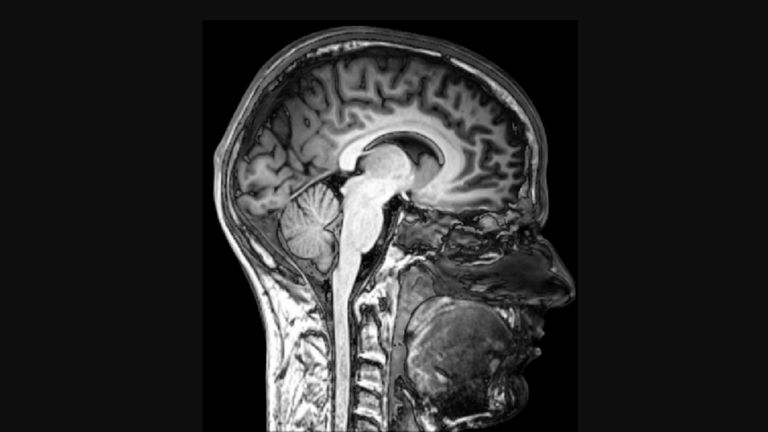

Una oleada de ondas gamma se localiza en la zona cortical posterior del cerebro, la que usamos para ver, oír e incluso soñar. Imagen: Wikimedia

La actividad se concentraba en la zona cortical posterior. Esta zona del cerebro, cuando está activa, nos permite escuchar, ver y sentir cosas. Es una región cerebral que también se estimula cuando estamos soñando o sufrimos algún tipo de alucinación visual. Esa oleada de ondas gamma no son propias de una persona inconsciente o en coma, por lo que observarla en ese momento crítico antes de la muerte ha levantado muchas preguntas. En el cine se han mostrado esos últimos segundos de vida de muchas maneras, como una película sobre tu propia vida que pasa a toda velocidad o el icónico túnel con una brillante y evocadora luz al final.